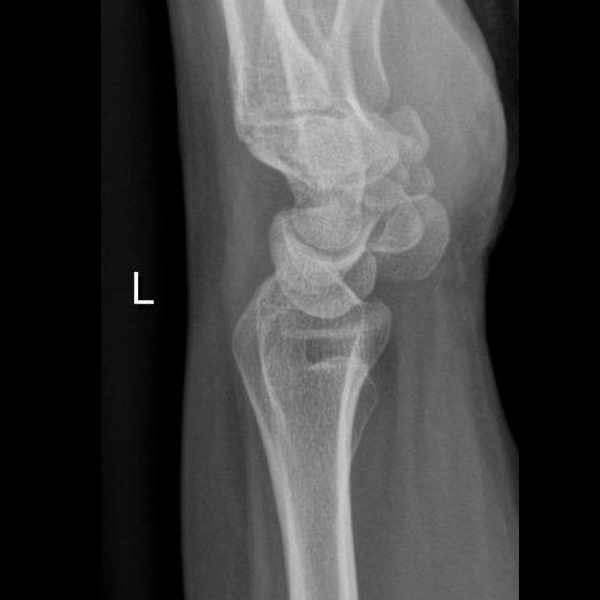

Learn the bony anatomy then test yourself